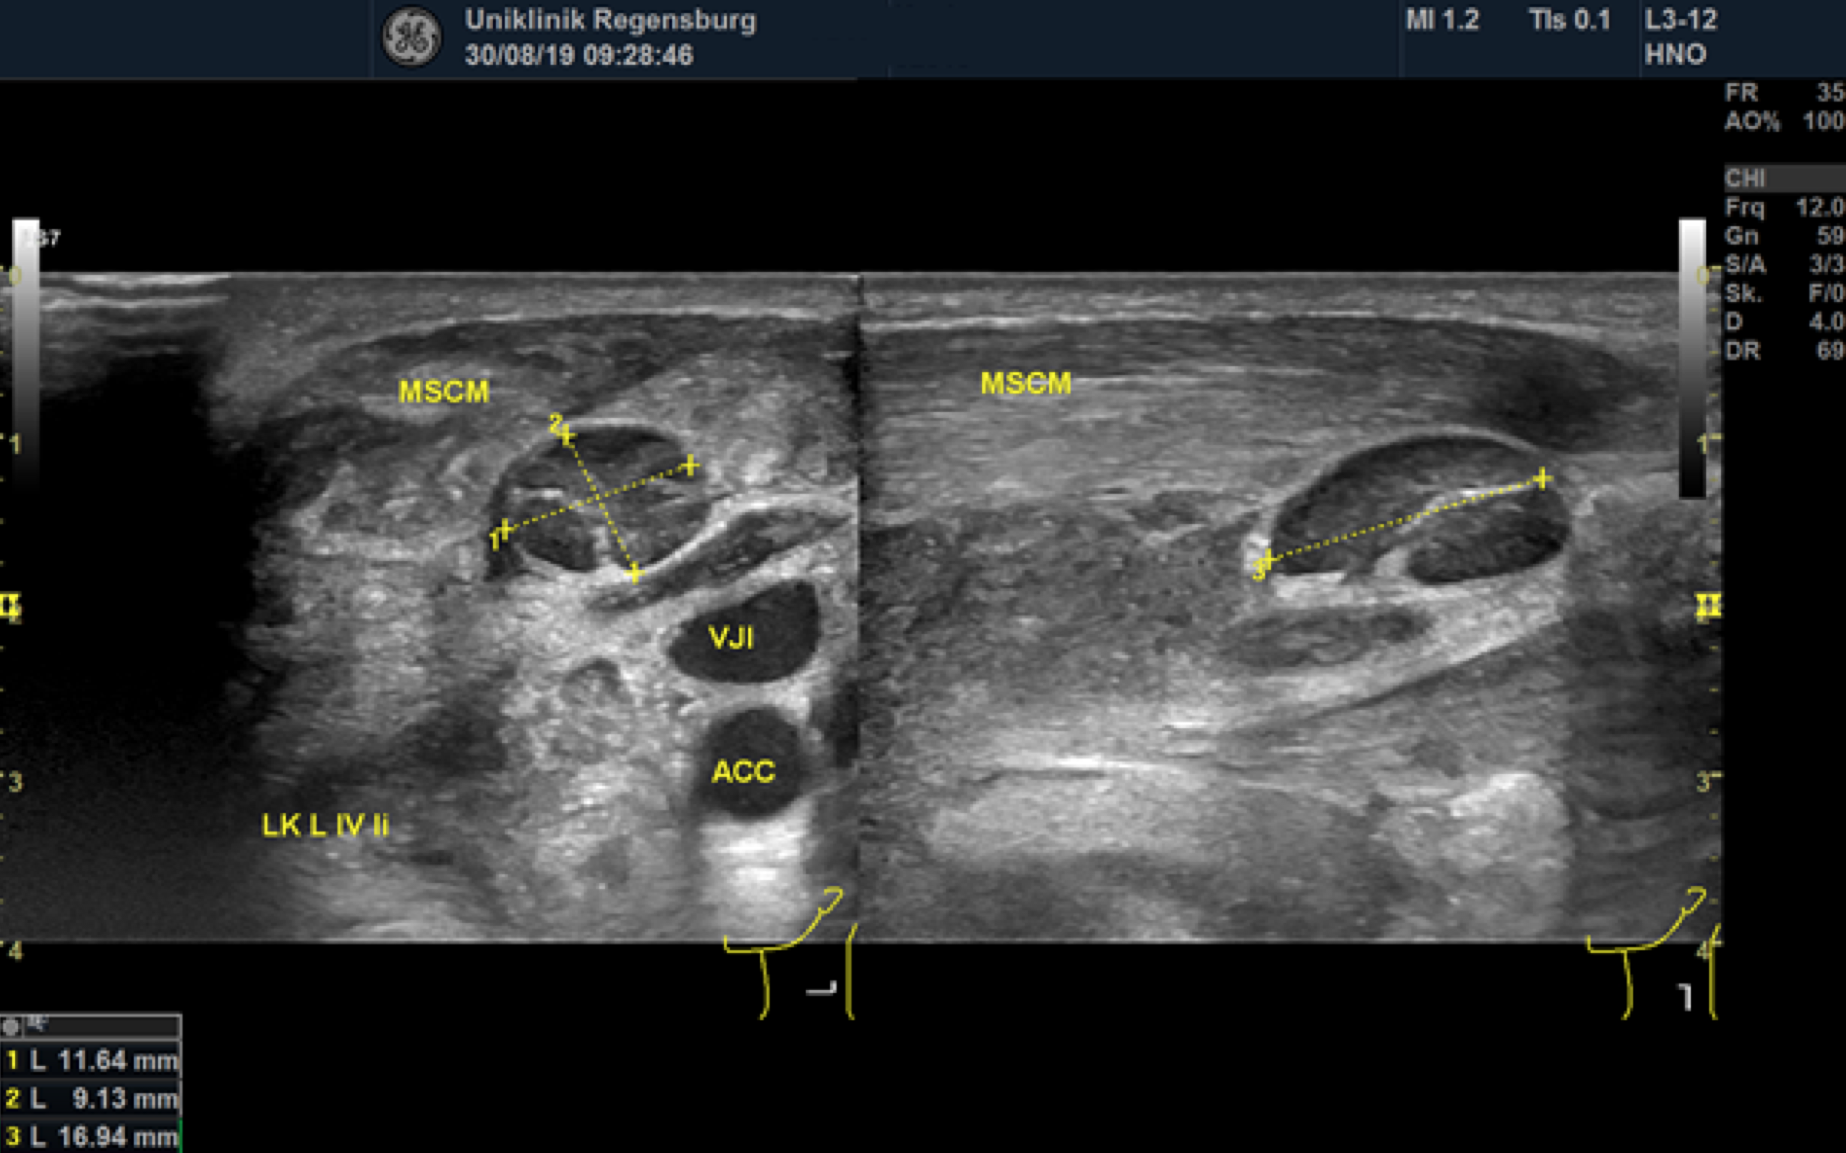

Preoperative ultrasonographic findings showed an oval hypoechoic inhomogeneous mass, approximately 4 x 3 x 1.5 cm in levels III to IV of the left side of the neck below the sternocleidomastoid muscle. (Fig. 1) The mass was partly indistinct to the adjacent tissue and demonstrated peripheral perfusion with no central vascularity. (Fig. 2) The surrounding soft tissues appeared oedematous and thickened. (Fig. 1 – 2)

Figure 1. Hypoechoic inhomogeneous mass partly indistinct from the adjacent tissue in Levels III to IV of the left neck; ACC = Common carotid artery; MSCM = sternocleidomastoid muscle.